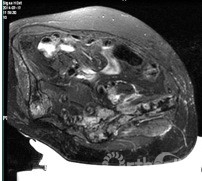

术中实时MR监控及动态测温图像

日前,继在国内率先应用磁共振引导超声聚焦术(MRgFUS)治疗子宫肌瘤后,国内第一例 MRgFUS术治疗转移性骨肿瘤病例在上海市第一人民医院获得成功。首例患者是一位32岁的腺泡样软组织肉瘤髂骨转移患者,该病理类型的肿瘤对放化疗均不敏感。 放射科王悍医生和骨科华莹奇医生对患者进行临床和影像学的综合评估后确认适合该项治疗。骨科沈嘉康医生完善了患者的术前检查和准备工作。麻醉科裘毅敏主任制定了针对性极强的个体化的麻醉方案,由游珊医生和陆文清执行术中麻醉。2014年7月16日,王悍医生和唐纳医生实施了对该患者的无创治疗手术。手术自下午17:30开始,全程约1个半小时,在放射科MRgFUS手术室完成 。术中,王悍医生通过控制聚焦超音波脉冲的激发对转移性骨肿瘤进行消融治疗,经实时温度监测,靶部位的温度达到65~100摄氏度,完全“烧毁”了局部肿瘤组织细胞。 整个过程患者无明显不适,实时心电监护、磁共振影像和体内多点测温的确保了手术的安全性和有效性。术后患者疼痛减轻,返回病房观察一夜后,次日便出院回家,在院之间不到24小时。7月17日,该团队又对另一例肺癌骨转移瘤患者成功实施了无创治疗。

治疗前磁共振图像

治疗后磁共振增强减影图像